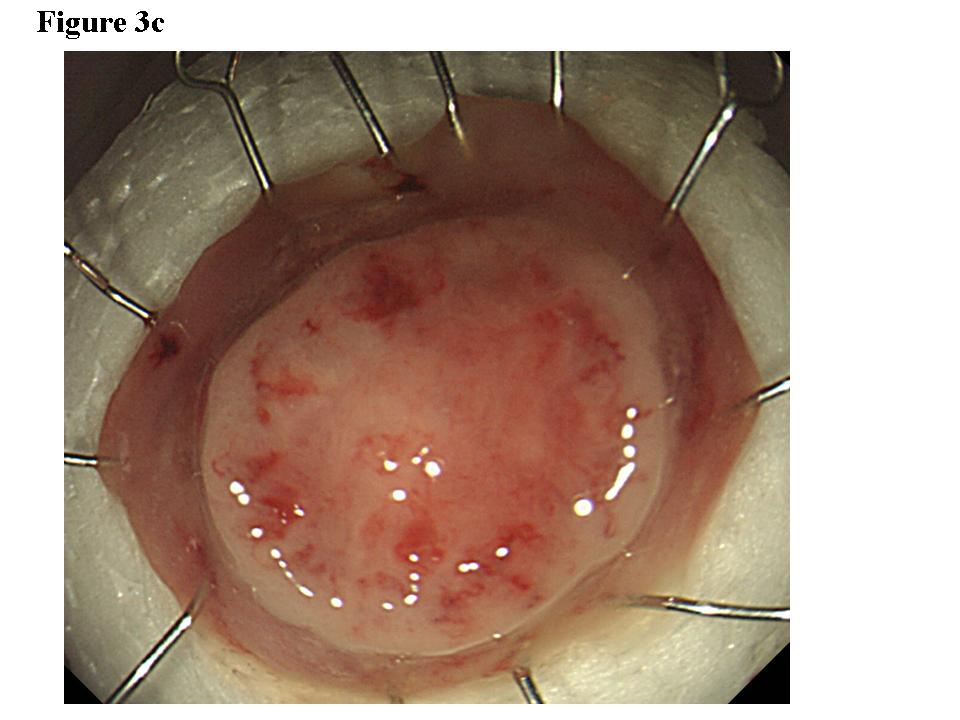

Figure 1.  Early rectal cancer lesion (EUS-M). a) Endoscopic features of superficial depressed type early rectal cancer lesion. b) The tumor was limited to be the first and second layers (EUS-M). c) Macroscopic feature of the tumor specimen.  d) The cancer invasion was limited within mucosa and muscularis mucosae.